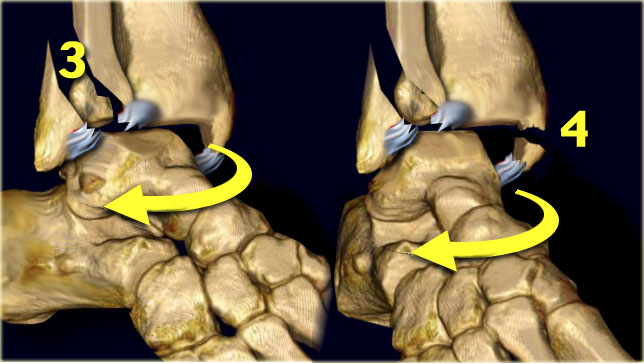

Here we see the different stages in the axial plane.

1. Medial avulsion fracture or rupture of the collateral band

2. Rupture of the anterior syndesmosis

3. Suprasyndesmotic rupture of the fibula due to rotation

4. Posterior malleolus fracture or rupture of the posterior syndesmosis

Scroll through the images.